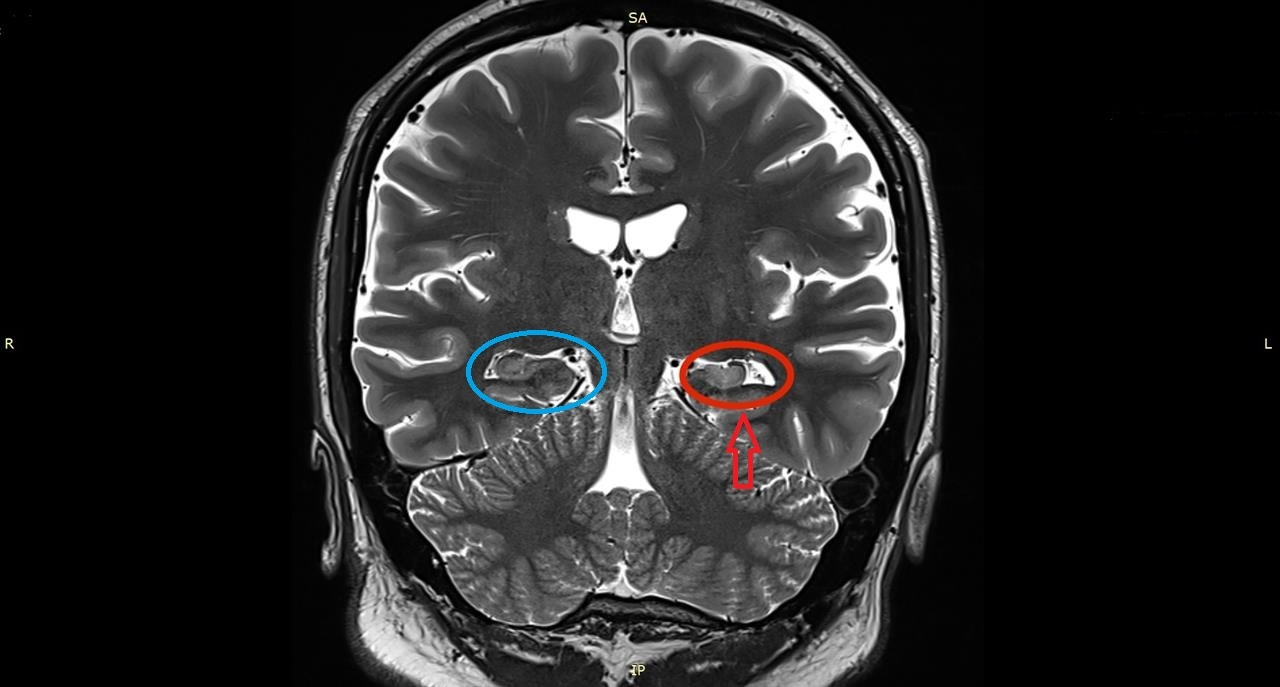

A closer look at my brain

I suffered a severe traumatic brain injury and was diagnosed with posttraumatic epilepsy early on in my recovery. Recently, however, I decided to see an epileptologist, or a neurologist who specializes in treating patients with epilepsy. Finding it weird that it never came to my mind to see an epileptologist, I decided to do so back in August of 2022 because I was having more frequent seizures. The doctor decided to order MRI scans of my brain; the MRI images showed left-sided MTS, and furthermore MTLE. One of the MRI images that shows the evidence of MTS is shown below.

The white tissue that the arrow is pointing to is scar tissue, indicative of left-sided MTS